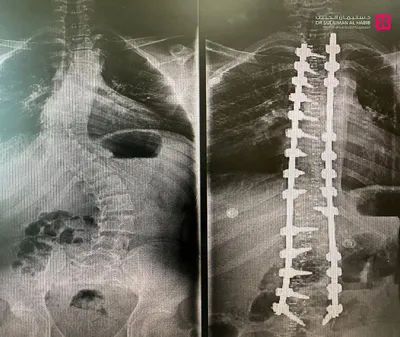

وأوضح د. عبدالجبار الحاصل على الزمالة الكندية، أن المراجع خضع فور وصوله للمستشفى لفحوصات دقيقة، شملت الأشعة السينية والرنين المغناطيسي، والتي أظهرت وجود ميلان وتحدب متزايد يتطلب تدخلاً جراحيًا عاجلًا. وبعد دراسة الحالة بشكل شامل، تقرّر إجراء عملية لتصحيح التشوّه وتحسين المظهر الخارجي للظهر.

وأضاف أن العملية استغرقت 4 ساعات، وأُجريت تحت المراقبة العصبية الدقيقة، وشملت تصحيح العمود الفقري على امتداد 14 فقرة عبر تثبيتها ودمجها باستخدام أحدث أنظمة التثبيت الجراحي، إضافة إلى إعادة توازن الكتفين وتناسق الخصر، وأسهم في نجاح العملية توفّر أحدث الأجهزة الطبية وكوادر طبية وتمريضية عالية التأهيل.